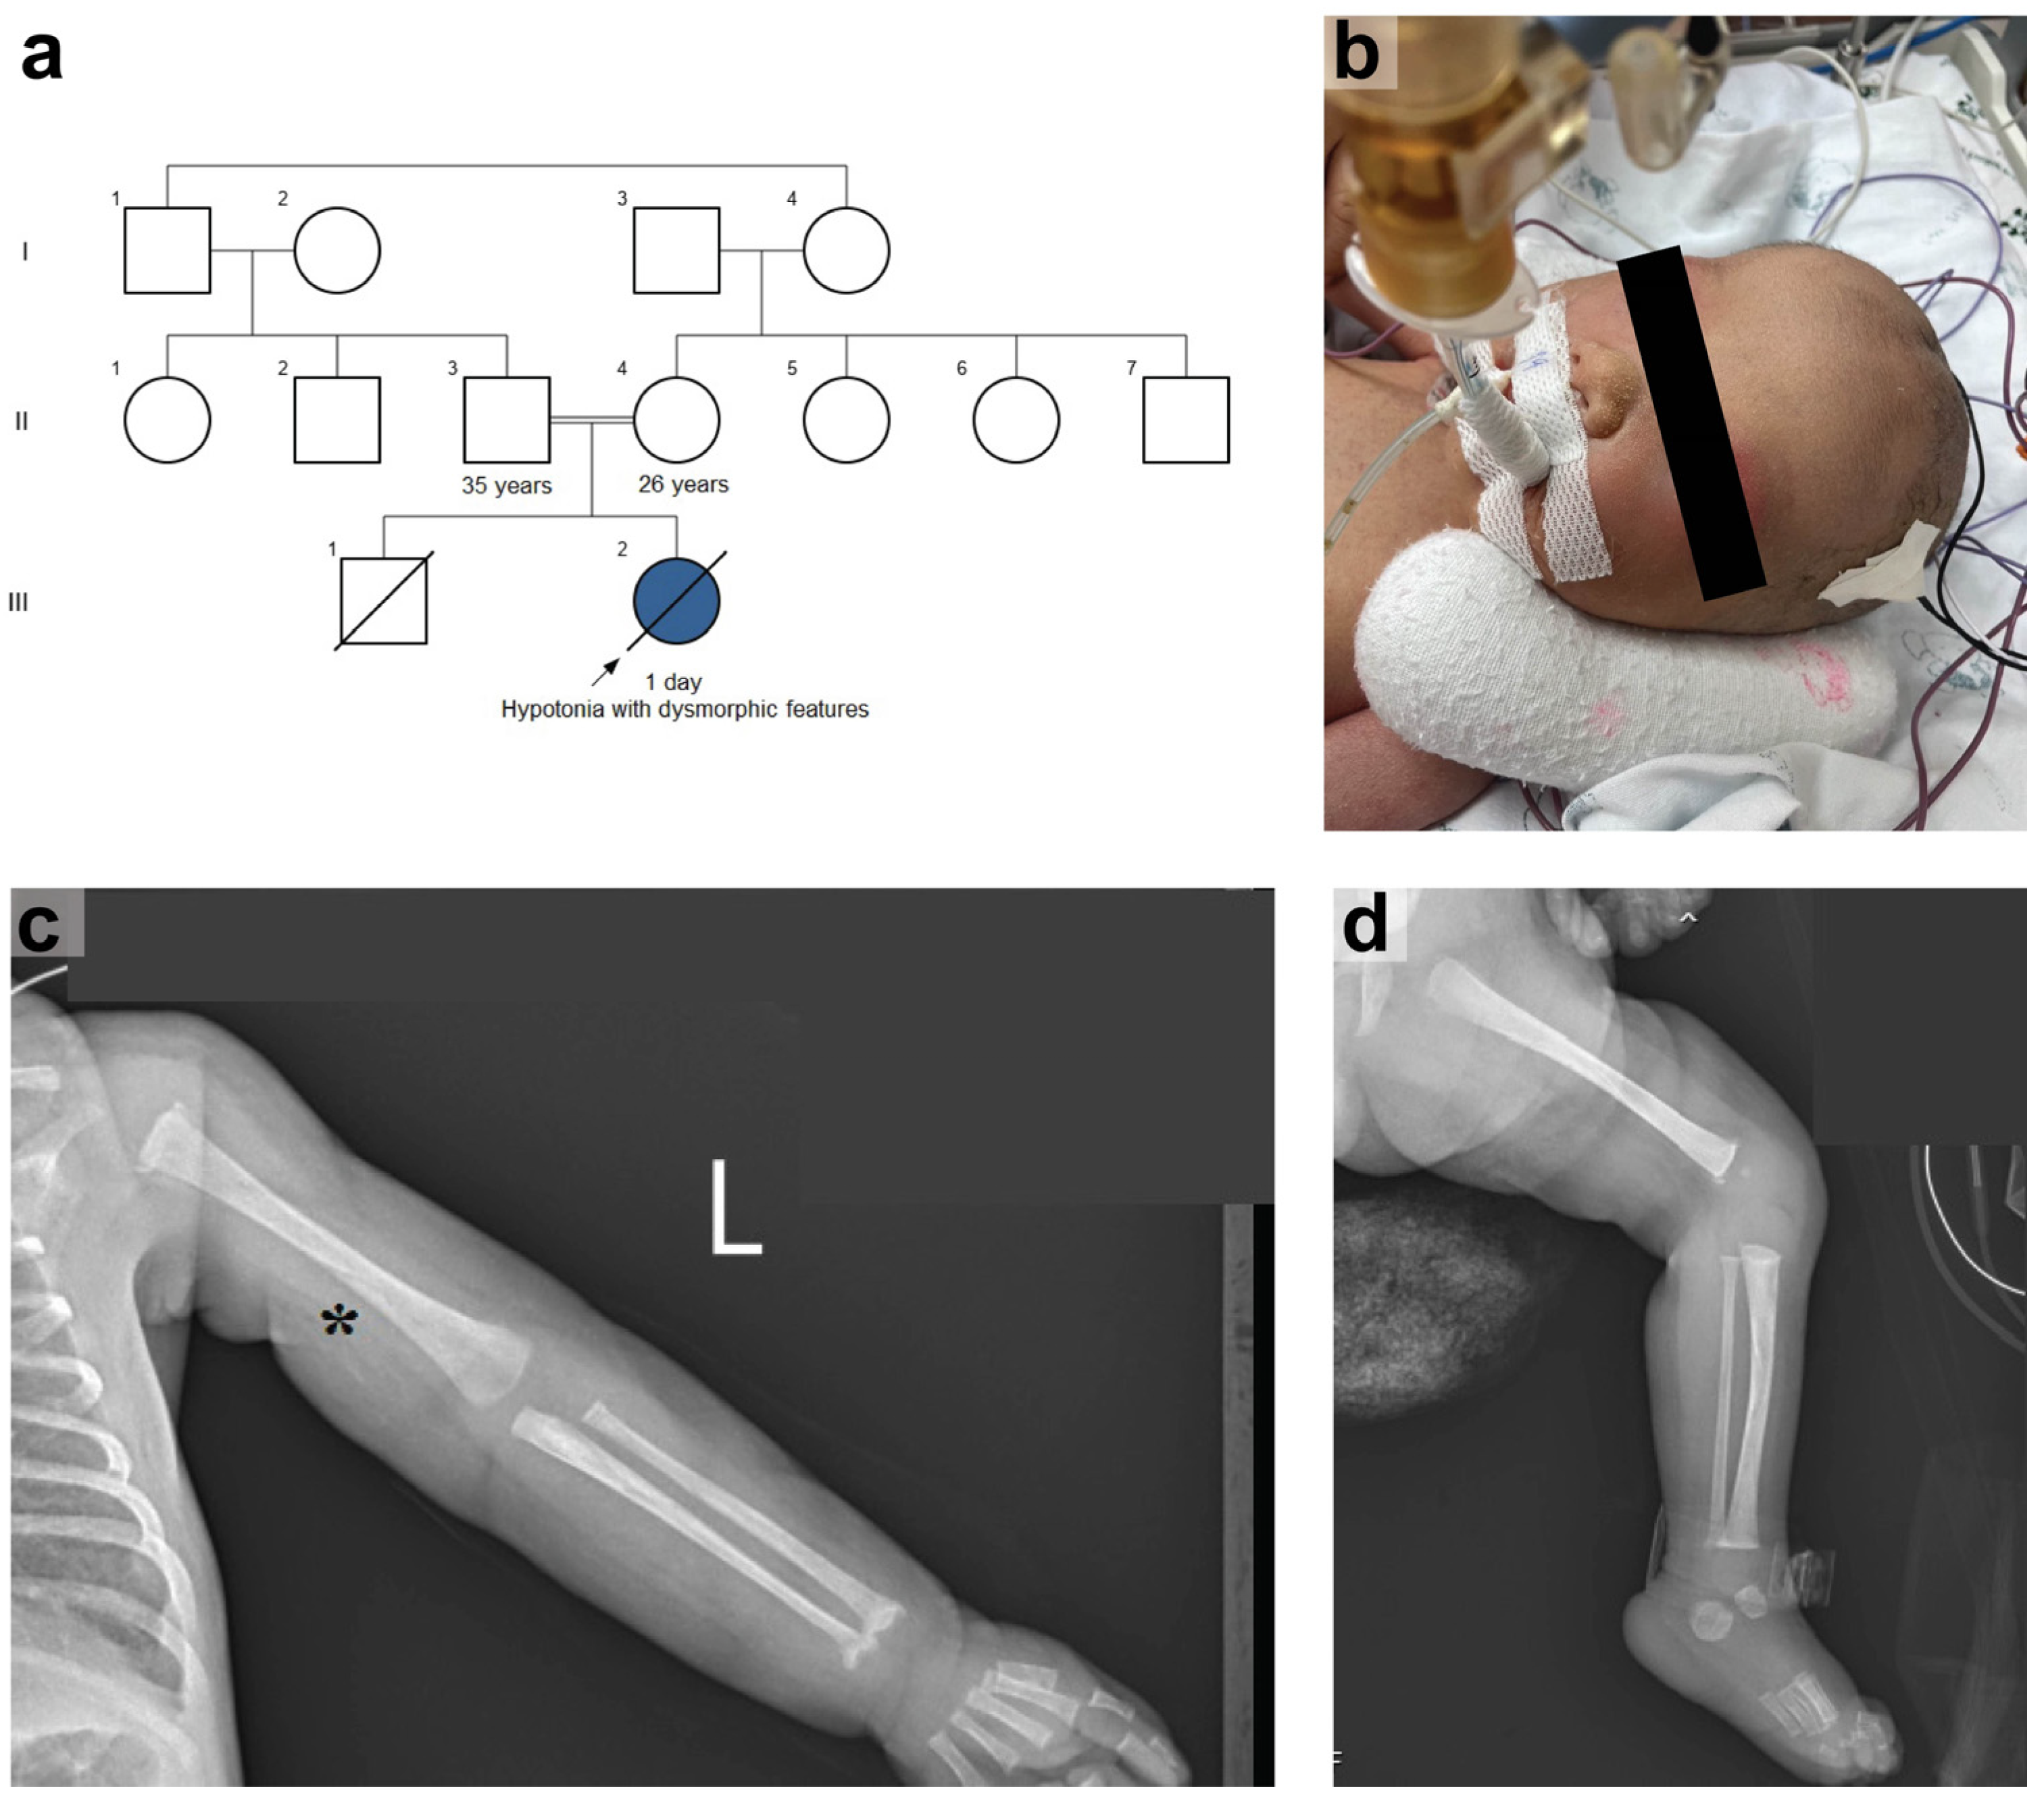

2.1. Case Report